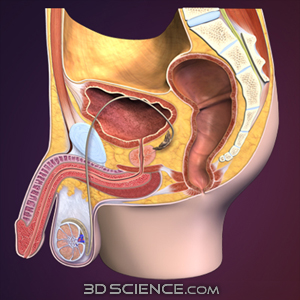

男性生殖器 断面図のイラスト素材

男性生殖器断面人体図 名称付き メディカルイラスト図鑑 無料の医療 美容素材集

男性生殖器 断面図のイラスト素材

男性生殖器断面人体図 名称付き メディカルイラスト図鑑 無料の医療 美容素材集

男性生殖器 断面図 Stock Illustration Adobe Stock

男性生殖器 断面図のイラスト素材

男性生殖器 断面図のイラスト素材

人体模型 男性骨盤 正中断面模型